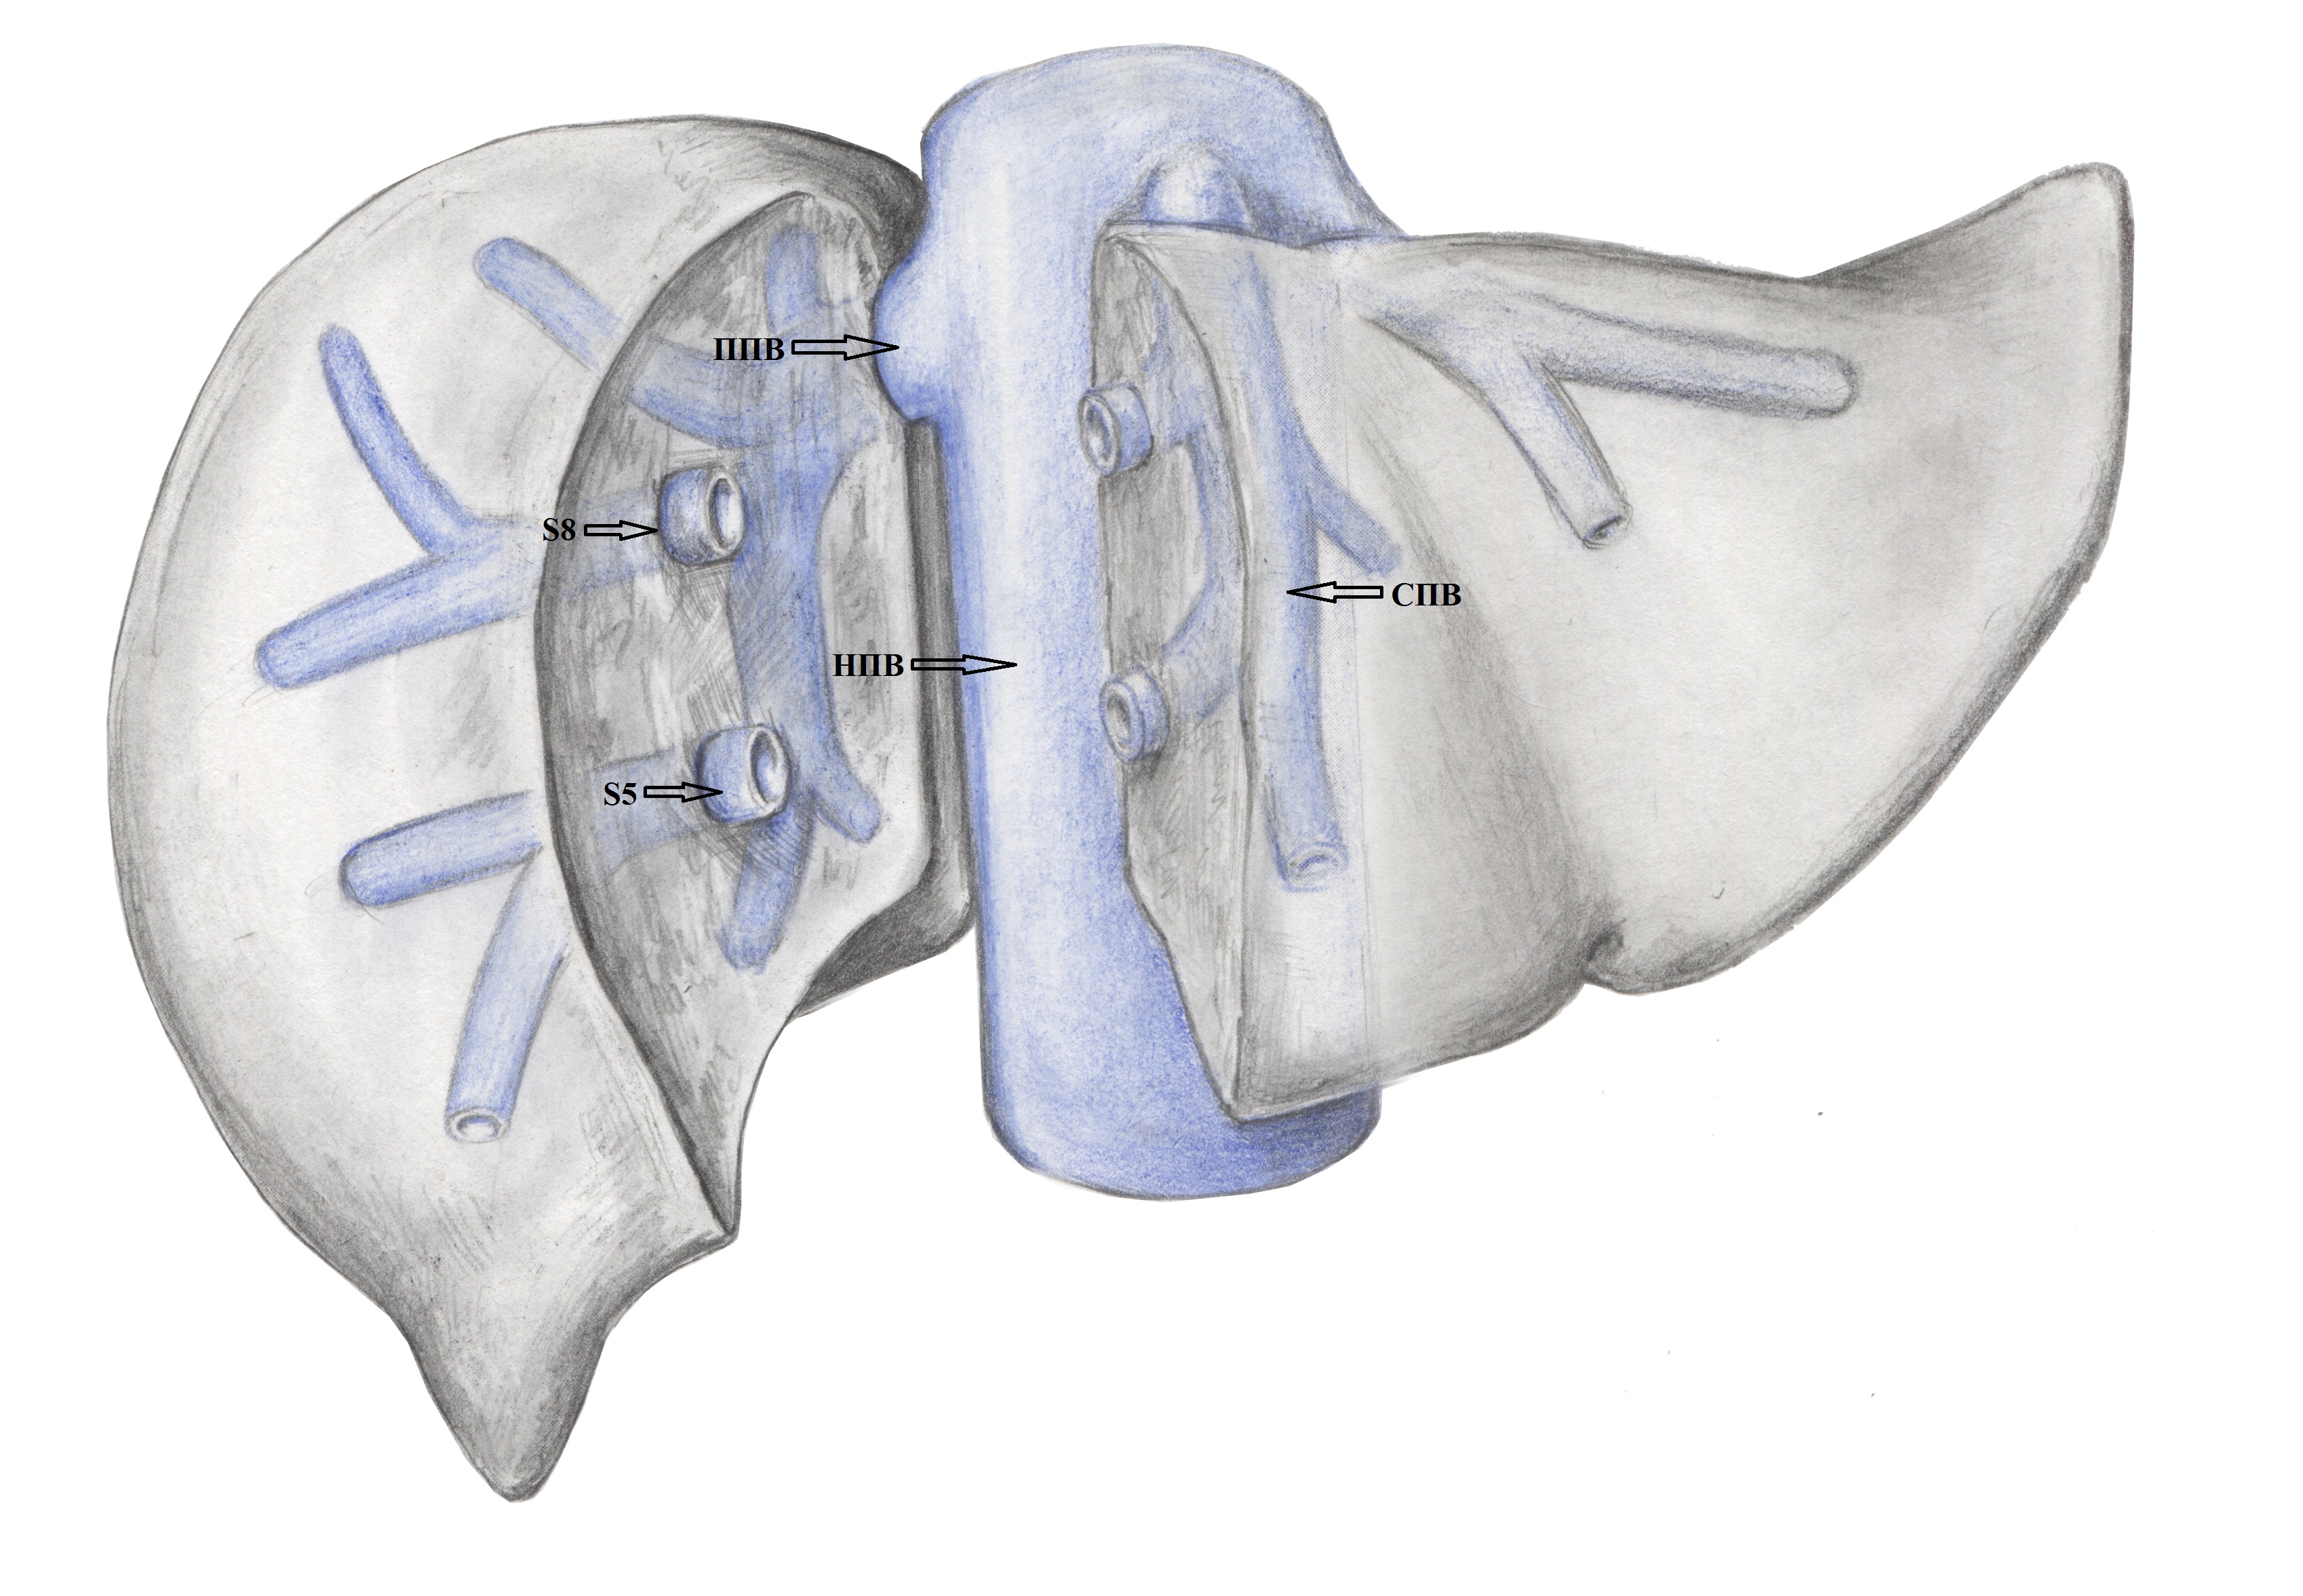

5. Тип B (схема). | |

| Тема | ||

| Тип | Исследовательские инструменты | |

Посмотреть

(1MB)

|

Метаданные ▾ | |